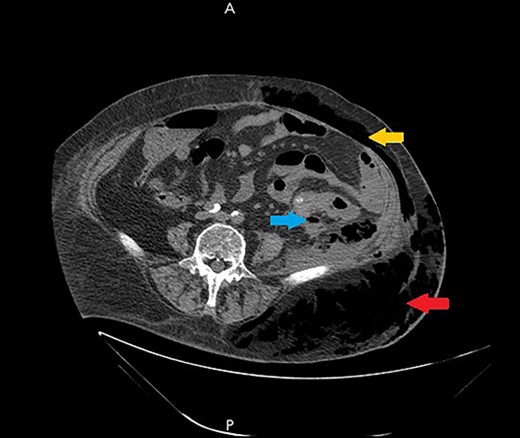

Ultrasound showed extensive subcutaneous soft tissue edema with hyperechoic areas seen in the proximal anterolateral part of the thigh. The initial diagnosis of the condition was a left iliopsoas abscess. Due to the severity of the patient’s symptoms, a non-contrast abdomen and pelvis computerized tomography (CT) scan was done (Fig. 3), which showed a large amount of subcutaneous emphysema within the left flank soft tissues that wrapped anteriorly along the left lower lateral abdominal wall with a small tract of air extending from the left retroperitoneum posterior to the left kidney and extending along the left iliopsoas muscle inferiorly. A skin defect with the underlying abscess collection and air–fluid level was noted (Fig. 4). Another CT scan section saw a soft tissue mass lesion at the distal descending colon (Fig. 5). The abscess drainage was done under CT guidance.

A non-contrast abdomen and pelvis CT scan, which shows a large amount of subcutaneous emphysema within the left flank soft tissues (lower arrow) that wrapped anteriorly along the left lower lateral abdominal wall into the anterior subcutaneous soft tissues of the left lower quadrant (upper arrow). There was also a small tract of air extending from the left retro peritoneum posterior to the left kidney and extending along the left iliopsoas muscle inferiorly (middle arrow).

A non-contrast abdomen and pelvis CT scan, which shows a skin defect with underlying abscess collection and air–fluid level, with significant subcutaneous air collection.